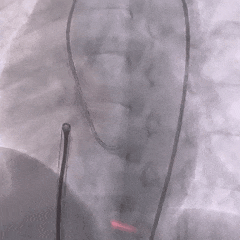

术中造影

术中造影复测缺损左室面破口3.9mm,隧道长11.37mm,判定为长隧道型室间隔缺损。

DSA下推出左盘

左盘展开后,后撤输送系统使盘面贴靠室间隔,再轻拉成型线使盘面成型

封堵器未锁定时造影,确认封堵器位置形态正确